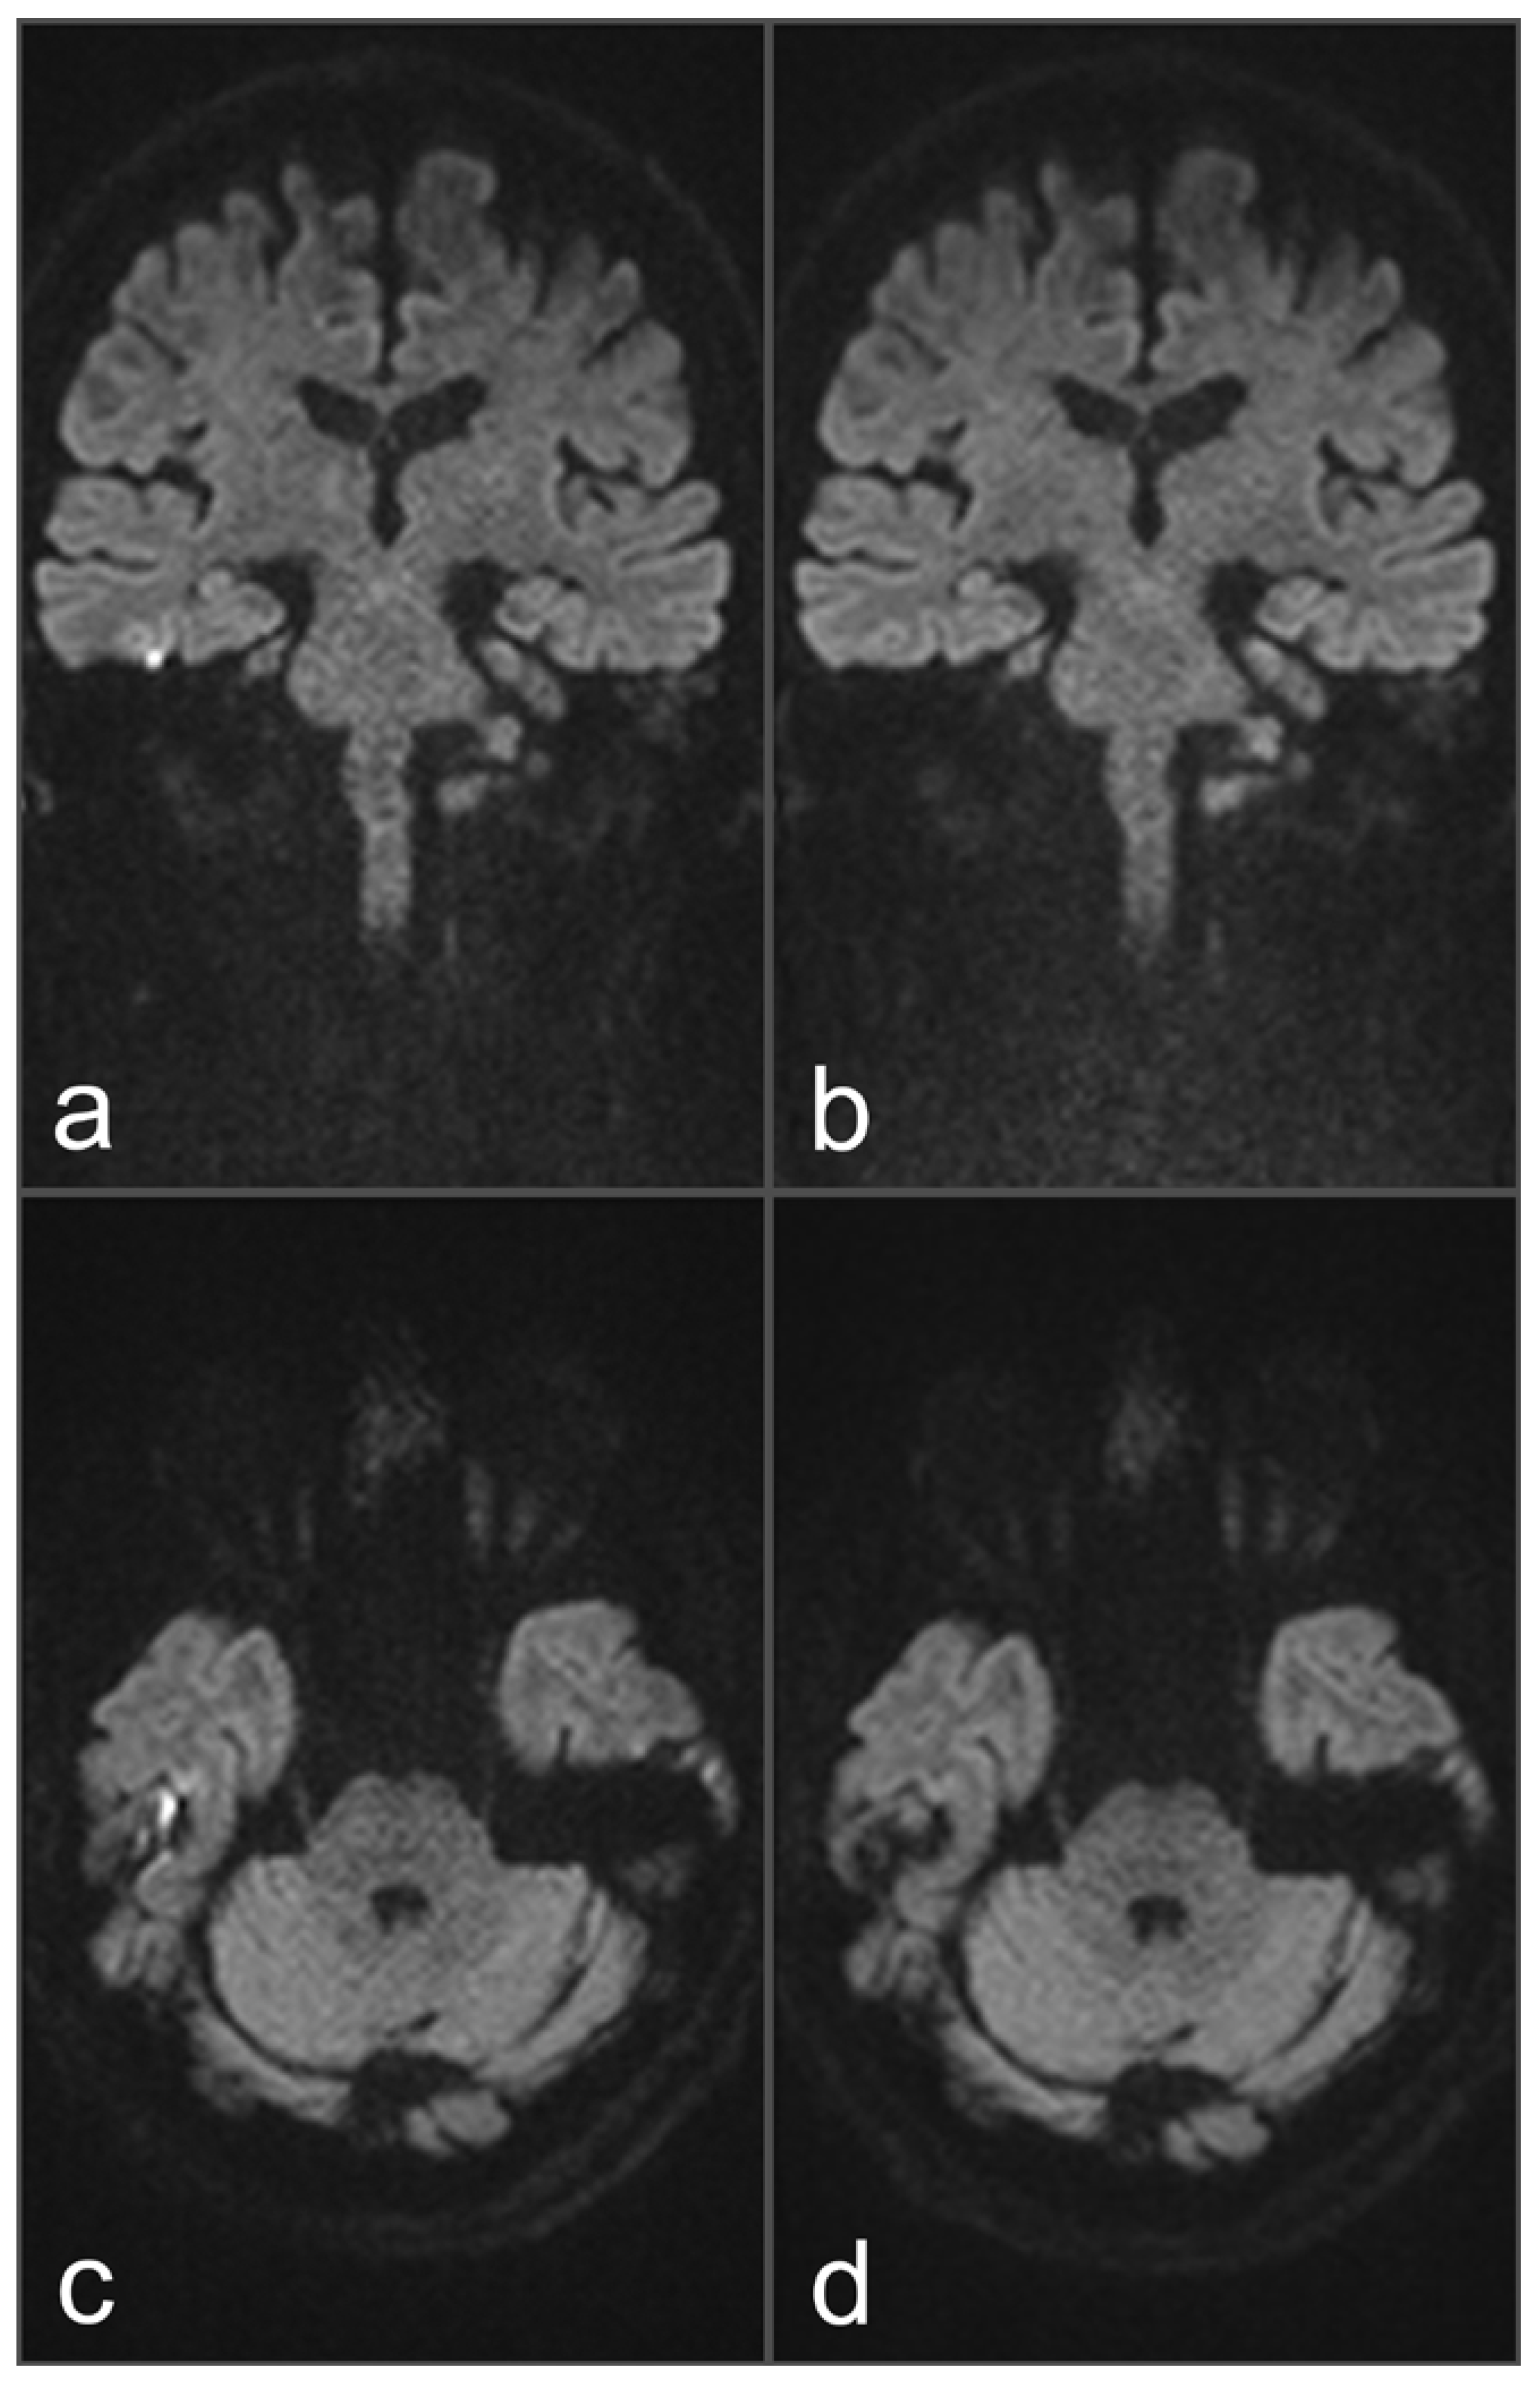

Figure 3. Images of a 54-year-old patient with a suspected cholesteatoma on the right side. (a) and (d) tseDWI (axial and coronal slice orientation). (b) and (e) uncorrected rsDWI (axial and coronal slice orientation). (c) and (f) top-up-corrected rsDWI (axial and coronal slice orientation). tseDWI images show an elongated hyperintense middle-ear lesion on the right side, which could be confirmed as a cholesteatoma after histopathological examination. The lesion is hardly visible in both uncorrected rsDWI images (especially on the axial images) and exhibits a geometrical distortion with a bent-like appearance on both slice orientations. Additionally, two punctiform hyperintensities are visible on both sides at the height of the temporal cortex. Both hyperintensities are missing on the tseDWI and the topup-corrected rsDWI images, strongly indicating that these hyperintensities represent artifacts. On the topup-corrected rsDWI images, the cholesteatoma on the right side exhibits a better contrast compared to uncorrected rsDWI, and geometrical distortions are comparably minor. Additionally, topup-corrected rsDWI does not show the above-described likely false-positive lesions at the border zone between bone and brain tissue.